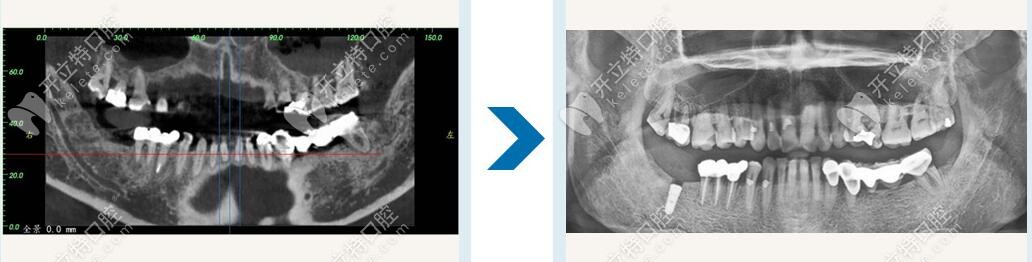

南寧柏樂口腔種植牙修復(fù)

Locator就是低平的牙槽骨上種植2-4顆種植體,通過種植體外接扣鎖的形式增加半口義齒的固位,一般種植后要讓種植體穩(wěn)定3-6月,然后在上外接裝置前一個(gè)月做半口義齒修復(fù),試戴一月,再進(jìn)行連接修復(fù)。